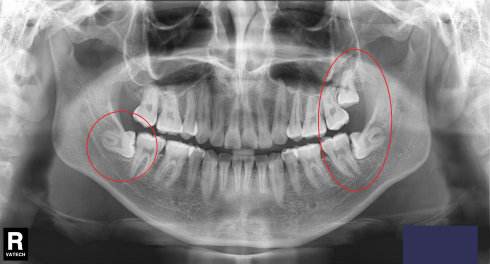

原因就是人类的进化,食物精细化,脸逐渐变窄,颌骨缩小,整个口腔呈慢慢变小的趋势。但是你要知道牙齿的数目和大小没有变化,而且智齿长出来比较晚,等它长出来的时候,其他28颗牙齿已经先入为主了,空间基本占满了,所以智齿没有足够的空间,只能以各种姿势出现在口腔中。横着、斜着、躺着、竖着、歪着、挤着,怎么舒服怎么来。

这图片是阻生智齿,也就包括横着长的智齿拔除,会比较复杂些,平常简单的拔牙就是用工具将牙齿拔掉,不用缝线,上个药就搞定啦。